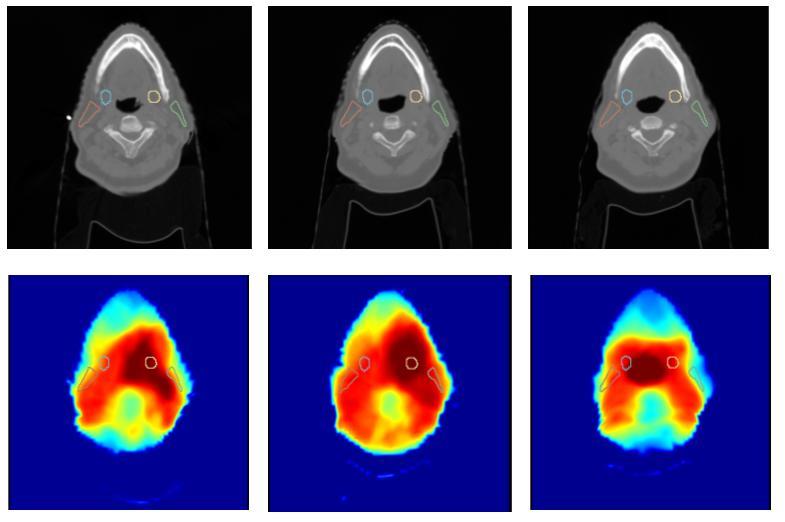

The high-resolution CAM module provides detailed spatial explanations of model predictions. Unlike traditional CAM methods that produce low-resolution activation maps, our approach generates high-resolution visualizations that precisely localize anatomical regions contributing to prediction. This is achieved through a specialized upsampling strategy that preserves spatial details while maintaining semantic meaning.

Our framework demonstrates superior performance in xerostomia prediction while providing clinically meaningful interpretations. The anatomy normalization significantly improves model generalization across diverse patient populations. The high-resolution CAMs successfully identify known risk factors such as parotid gland dose distributions and reveal novel spatial patterns associated with xerostomia risk.